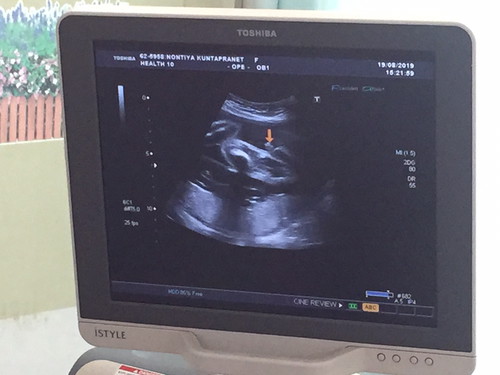

อันนี้ใช่จู๋น้องมั้ยคะ หมอบอกเป็นเพศชายแต่ตอนซาวด์แม่ดูไม่ออกเลย5555

ใช่เลยค่ะ จู๋มาเต็มมาก

ใช่จ้าา